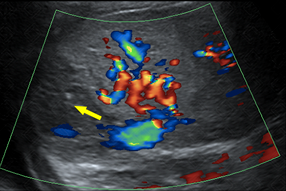

Descrição das figuras: Paciente pediátrico, portador de anemia falciforme com dor em hipocôndrio esquerdo. Na ultrassonografia observa-se lesão em cunha, com formato triangular, hipoecoico e, durante a avaliação com Doppler colorido, não há fluxo nesta região (setas vermelhas e amarela), confirmando a possibilidade de isquemia/infarto.

• Ultrassonografia do abdome: Observaremos lesão em cunha, com formato triangular, hipoecoica e, durante a avaliação com Doppler colorido, não há fluxo nesta região (setas vermelhas e amarela), confirmando a possibilidade de isquemia/infarto (figuras acima) .